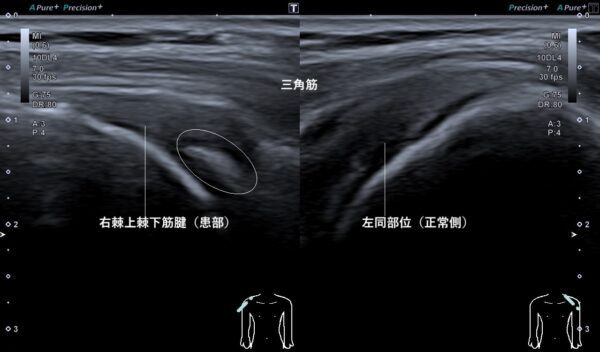

また、右肩に触れると熱感が強く、炎症が起きていることが推察されました。それらの所見から、超音波(エコー)画像観察を行うと右棘上棘下筋腱に石灰*(カルシウム)がたまっていました(画像、丸の中の白い箇所)。

*約2か月後、石灰は消失していました。